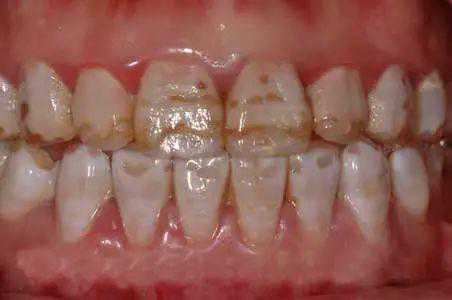

氟斑牙是指牙齿发育、矿化期间,机体摄入过量的氟引起牙釉质钙化不良损害,主要表现为牙釉质失去正常的光泽和透明度,出现不同程度的白垩样变、着色和凹陷缺损等病变,一旦形成残留终生,轻则影响美容,重则由于严重缺损或过早脱落,影响咀嚼消化功能危害健康。氟斑牙是地方性氟中毒最重要的表现。

氟斑牙▼